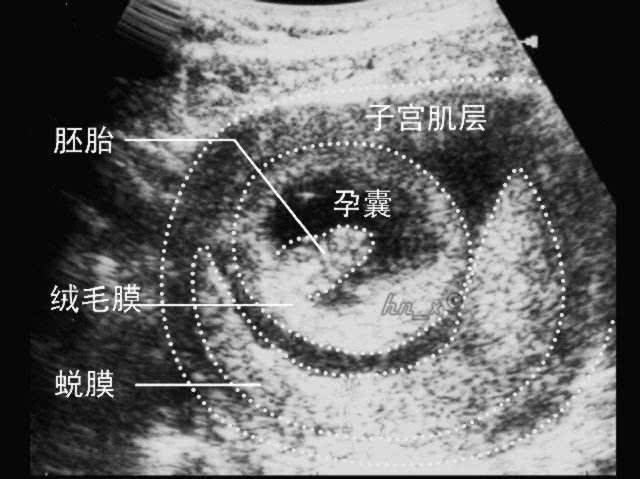

妇产科超声:胚胎着床位置及妊娠囊的超声表现,如何解读?

腹痛及其他病史,在孕7-8周进行超声检查确认妊娠状态,观察孕囊位置